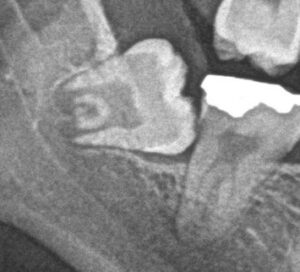

1. 横に向いて生えている、または骨の中に埋まっている(水平埋伏智歯)

特に、横に向いて半分だけ顔を出している親知らずは、汚れが溜まる「ばい菌の温床」になりやすく、手前の大切な寿命まで縮めてしまうため、早めの抜歯をおすすめしています。

横に向いて骨に深く埋まっている親知らずや、顎の太い神経・血管に極めて近い親知らずの場合、一般的な歯科医院では「うちでは抜けないので、大学病院や総合病院の口腔外科へ紹介状を書きますね」と言われることがよくあります。

• メリット3:事前の精密な3D診断(歯科用CT完備) 当院では、神経や血管の位置、根の曲がり具合などを立体的に把握できる「歯科用CT」を完備しています。認定医がこのCT画像を綿密に分析し、安全で確実な手術のシミュレーションを行った上で抜歯に臨みます。